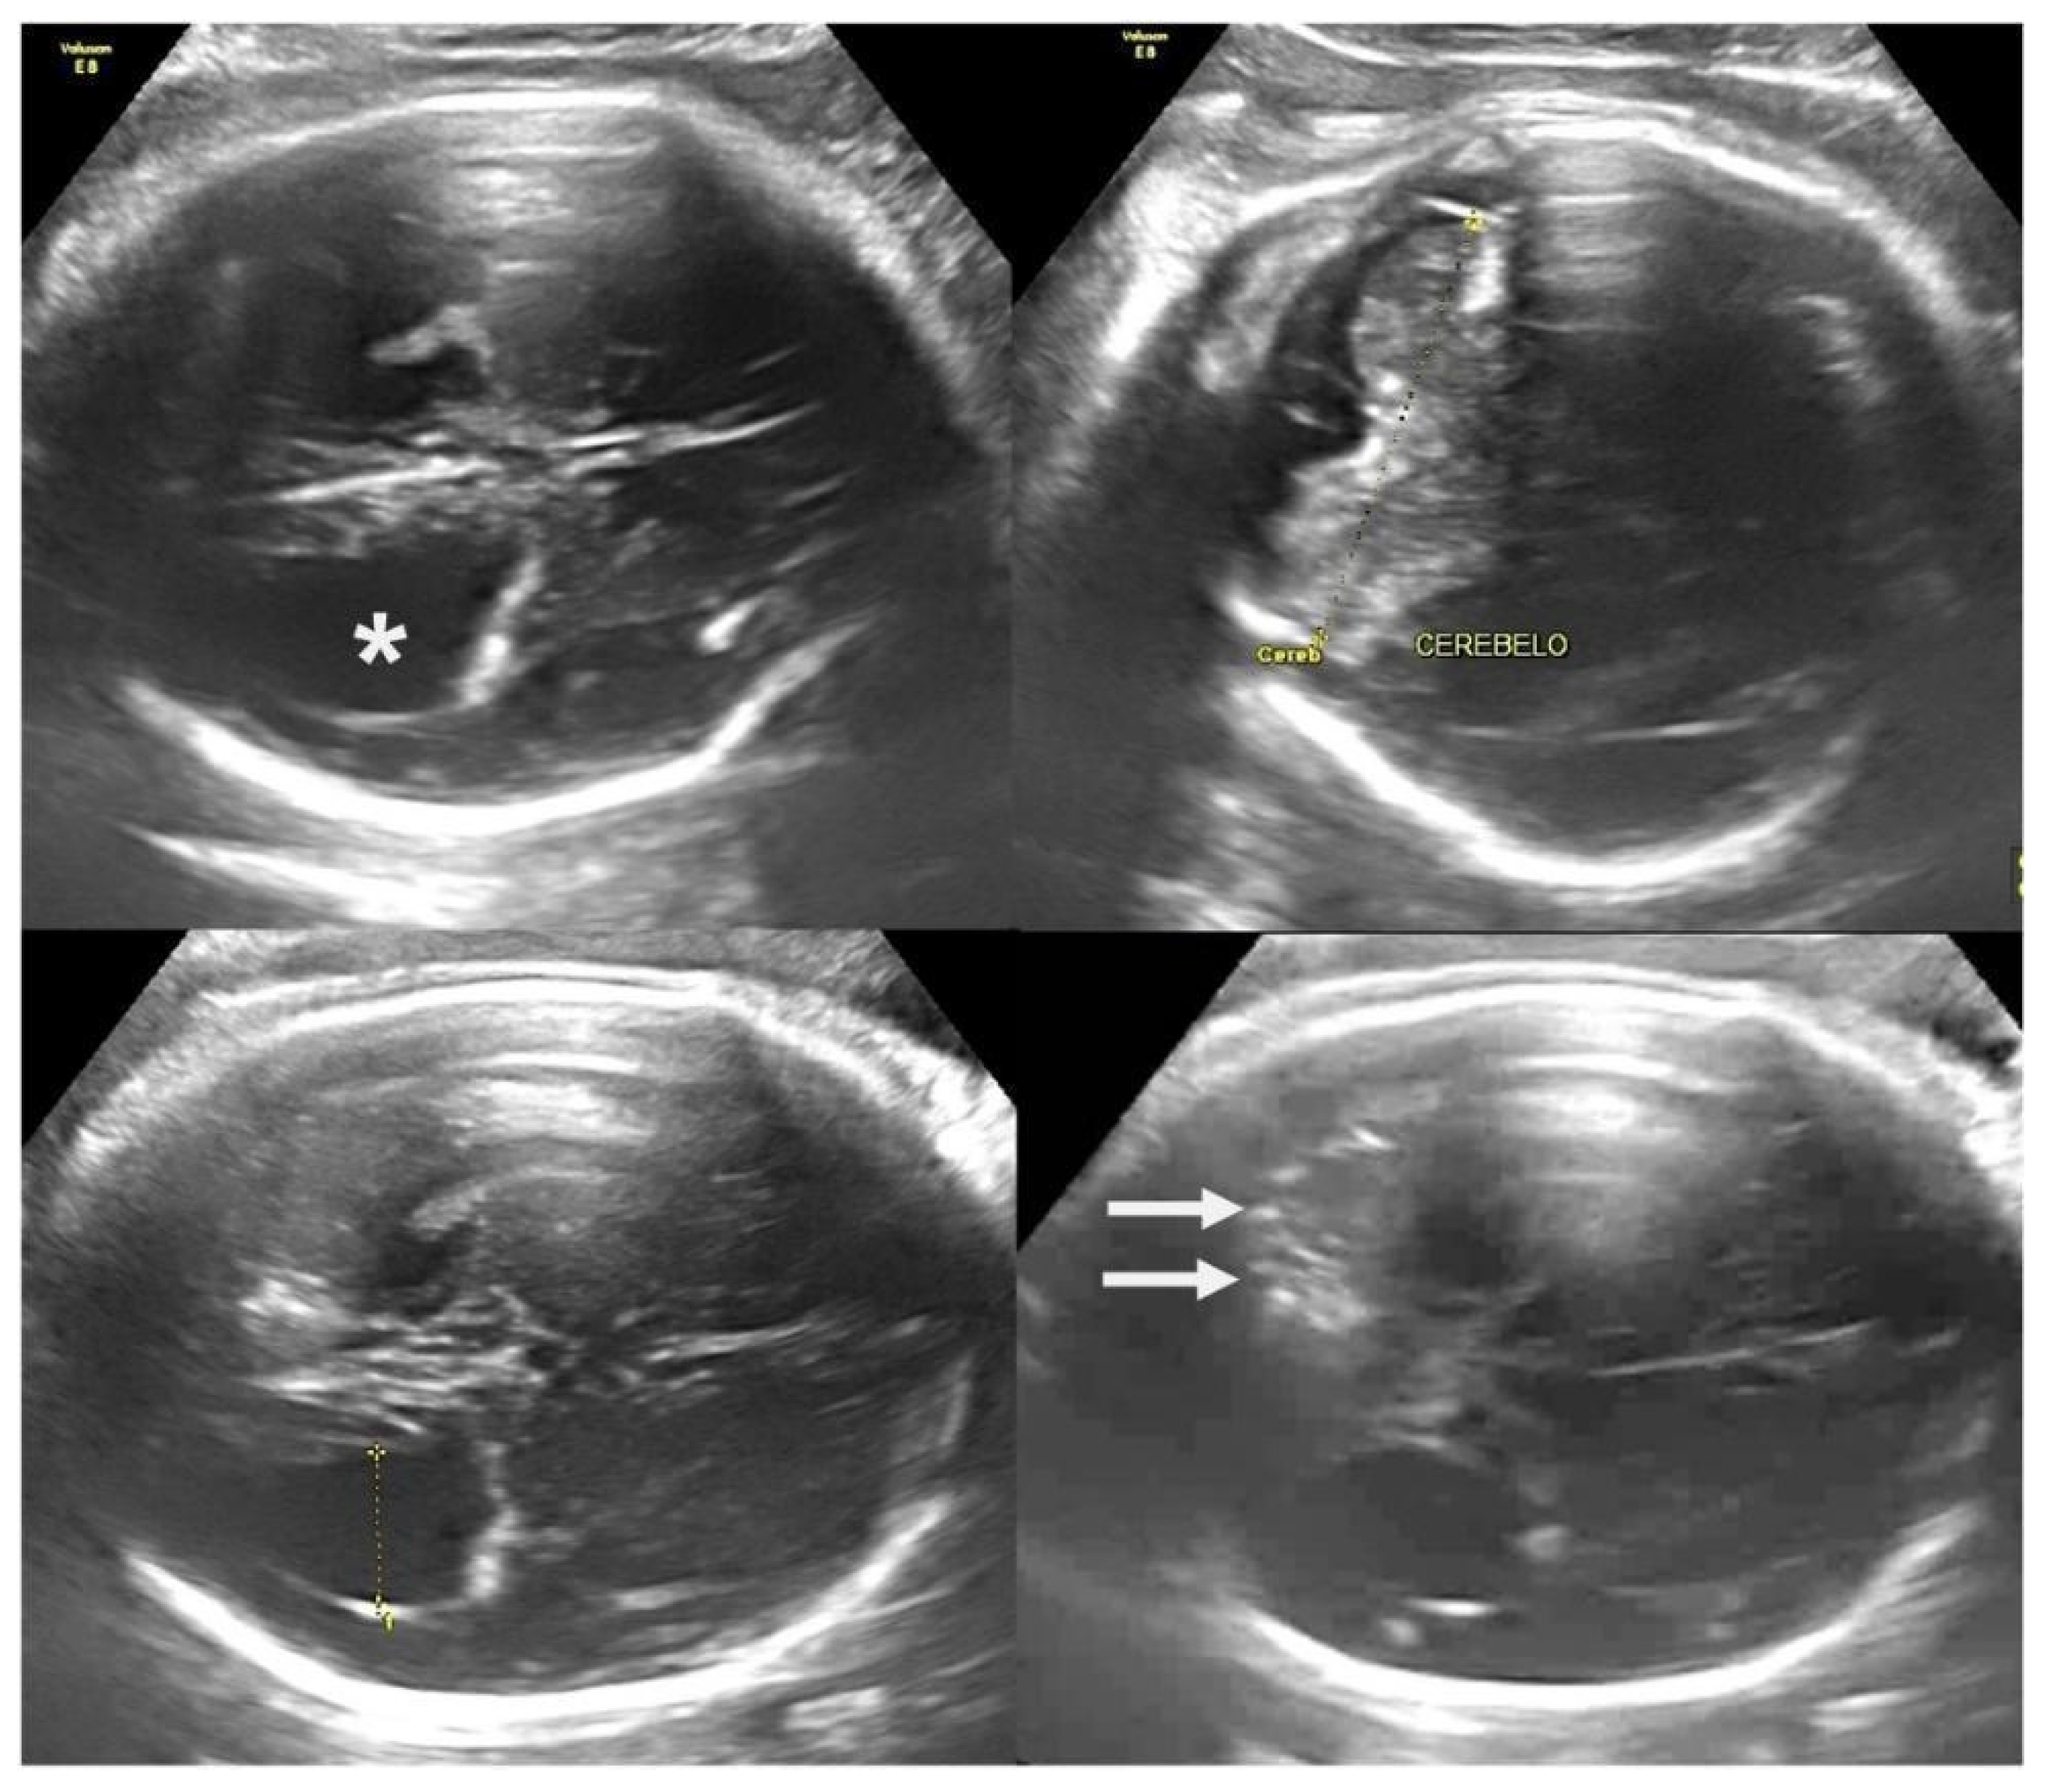

- Araujo Júnior, E.; Carvalho, F.H.; Tonni, G.; Werner, H. Prenatal imaging findings in fetal Zika virus infection. Curr. Opin. Obstet. Gynecol. 2017, 29, 95–105. [Google Scholar] [CrossRef] [PubMed]